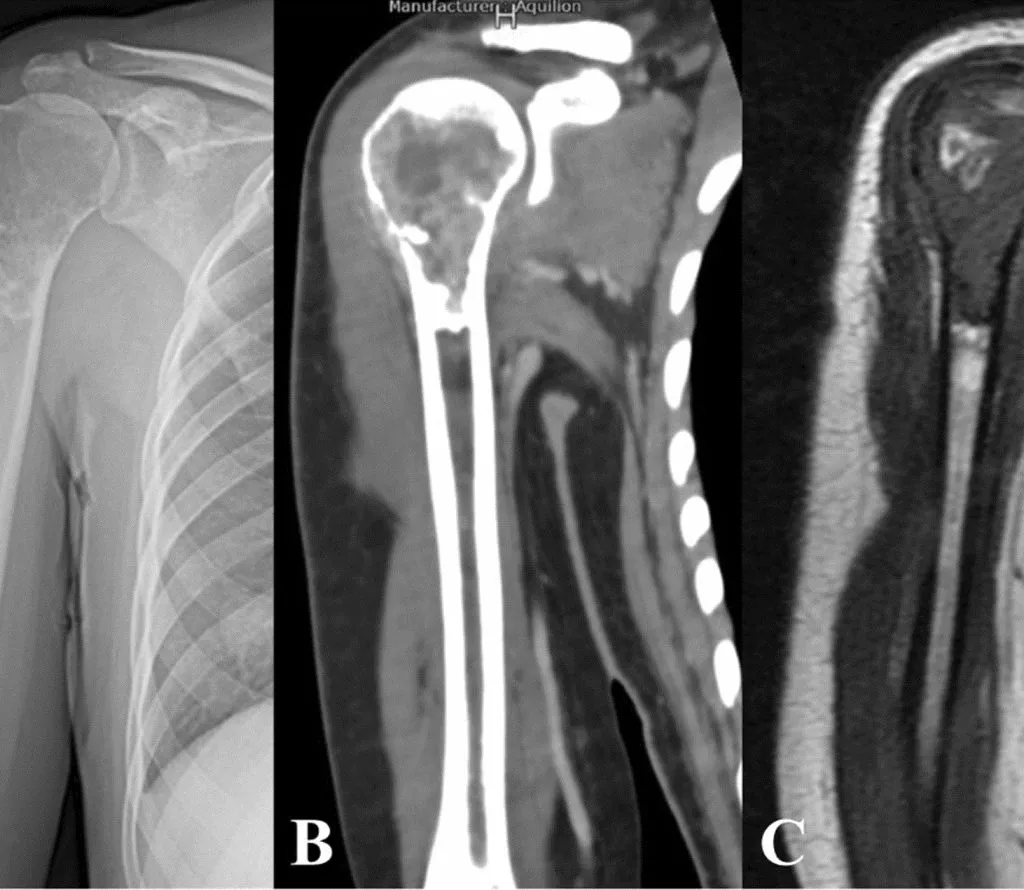

2. Proximal Humerus Tumours By Dr. Vivek Sharma | In conversation with Dr. Deependra

This is not just a tumour lecture—it’s a clinical roadmap.

Key Highlights:

🔹 Step-by-step understanding of proximal humerus tumours

🔹 Fusion of anatomy, clinical features, and surgical judgment

🔹 Dr. Sharma’s practical insights from years in ortho-oncology

🔹 Core learning points for your viva and clinics

Click Here to Watch the Video →